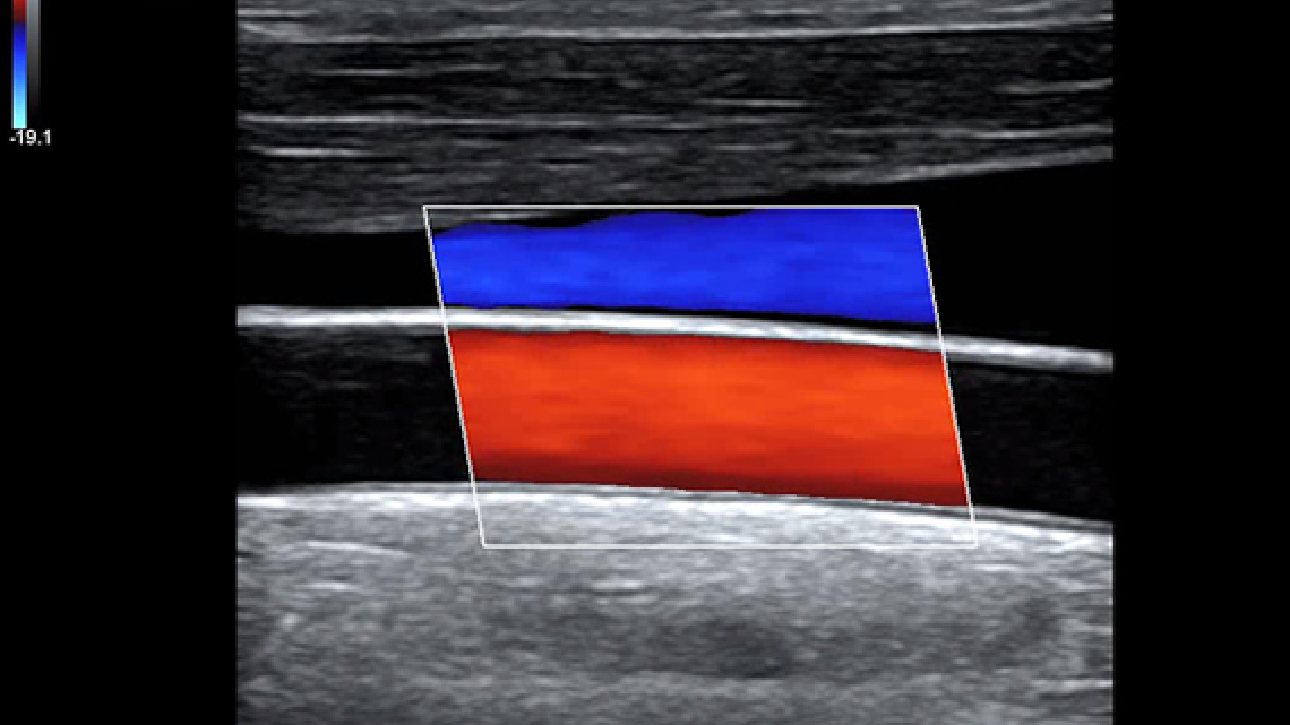

Smart Track

ItŌĆÖs Mindray unique feature to reduce repetitive, time-consuming scanning steps in vascular exams. Smart Track provides intelligent and real-time vessel tracking and real-time image optimization of Color and PW.